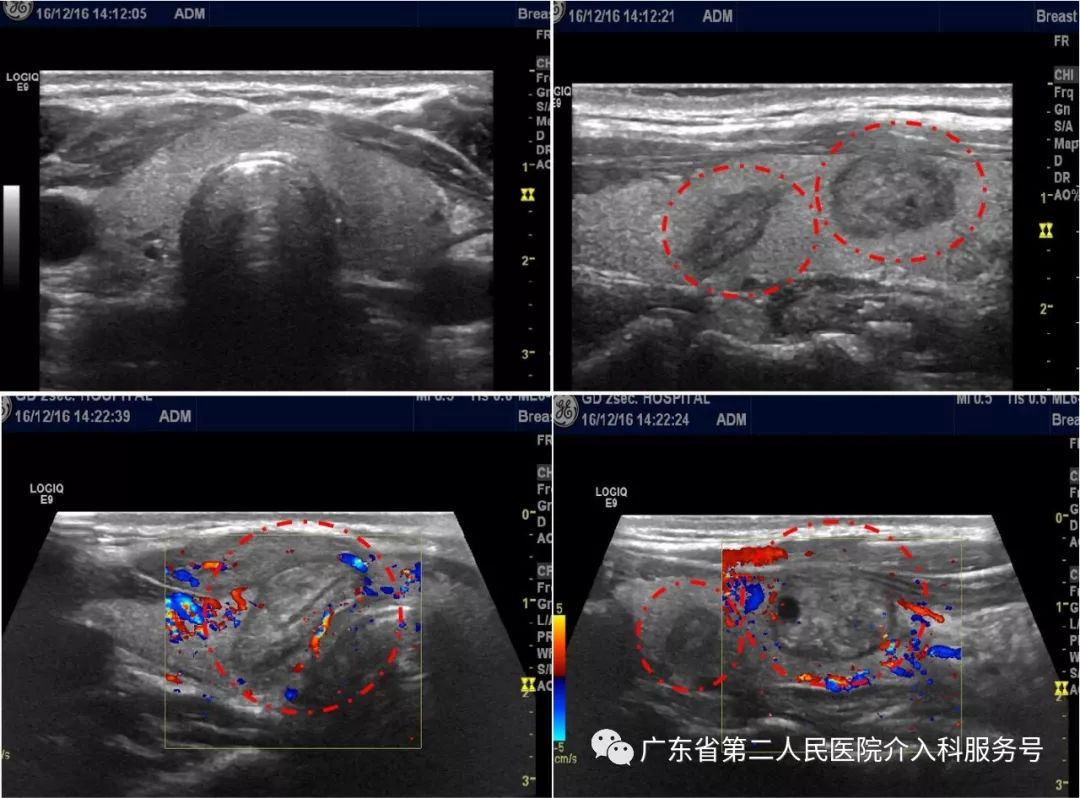

康女士发现她的颈部左侧凸出,在当地医院检查超声后发现是甲状腺长了个2公分的结节,医生建议治疗,康女士感觉甲状腺结节不疼不痒的则未治疗。一年后康女士到医院复查发现结节增大到2.5公分了,不能只观察,要采取治疗措施了,康女士听说中草药配合饮食调理可以治疗甲状腺结节,则自行服药治疗。随着时间推移,康女士吃饭、喝水时常感觉有东西卡喉,吞咽异物感明显,康女士到医院复查超声发现结节增大到3公分多了,结节内出现囊变坏死。当地医院没有微创技术,只能开刀手术切除治疗,颈部疤痕明显,康女士就到广州就诊。在我院门诊超声检查显示:康女士甲状腺长了3个结节,最大的结节3.2公分并且出现部分囊变坏死(如下图)。